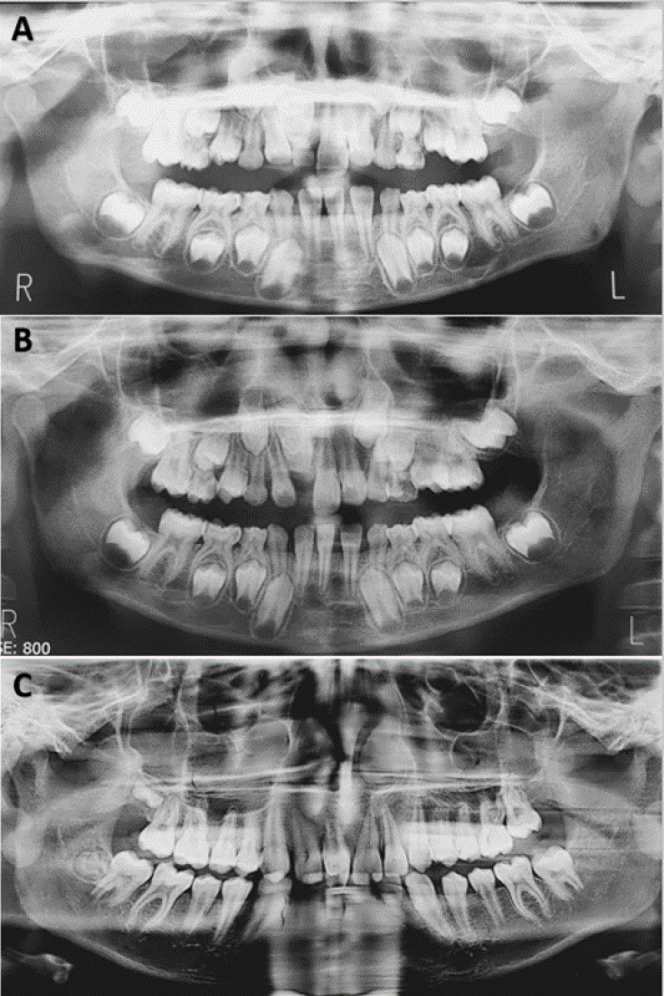

内凹牙是由于牙釉质和牙本质向牙髓内折叠而引起的发育异常。Oehlers的IIIa型牙槽内陷由于其复杂的解剖结构和经常与未成熟牙齿相关而面临重大挑战。本病例报告概述了一个非重要的未成熟上颌中切牙IIIa型牙槽内陷的非手术治疗,表现为慢性根尖脓肿和相关的上切牙创伤史。治疗包括彻底的化学机械清创,然后使用富钙混合水泥进行生物封闭。定期随访发现根尖周围病变完全消退。这个病例强调了精确诊断、个体化治疗计划和应用先进生物材料在解决复杂凹牙表现的重要性。成功的结果强调了非手术技术在保留未成熟牙齿的同时恢复功能和美观的有效性。

Dens invaginatus is a developmental anomaly resulting from the infolding of enamel and dentin into the dental pulp. Oehlers' Type IIIa dens invaginatus poses significant challenges due to its intricate anatomy and frequent association with immature teeth. This case report outlines the nonsurgical management of a nonvital immature maxillary central incisor with Type IIIa dens invaginatus, presenting with a chronic apical abscess and a history of trauma to the associated primary incisor. Treatment involved thorough chemomechanical debridement followed by bio-obturation using calcium-enriched mixture cement. Regular follow-ups revealed complete resolution of the periapical lesion. This case underscores the importance of precise diagnosis, individualized treatment planning, and the application of advanced biomaterials in addressing complex presentations of dens invaginatus. The successful outcome emphasizes the efficacy of nonsurgical techniques in preserving immature teeth while restoring function and aesthetics.